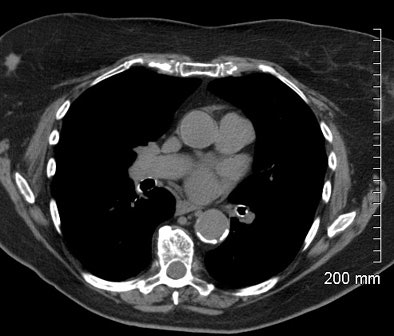

| Incidental breast cancer was detected at chest CT in a 65-year-old woman presenting for workup of an incidental nodule on chest x-ray. The patient's last screening mammogram was 18 months before CT. Image courtesy of Dr. Jeffrey Mendel. |